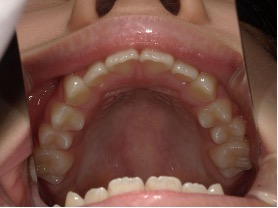

| 年齢・性別 | 8歳9ヶ月の女児 |

|---|---|

| 主訴 | 歯並びの乱れを気にされて来院された患者様です。将来的なスペース不足と歯のねじれ(翼状捻転)が懸念されました。 |

| 治療期間・回数 | 2年10ヶ月・19回 |

| 費用 | 430,000円(税別) |